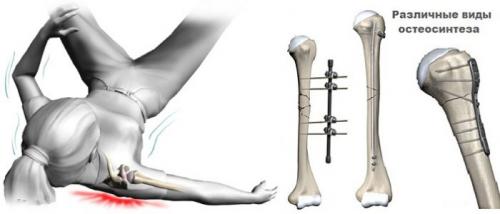

Остеосинтез плечевой кости реабилитация. Остеосинтез кости плеча

При сложных переломах с деформацией плеча, когда есть раздробление кости, правильным будет применение остеосинтеза плечевой кости. Эта операция проводится при невозможности совместить отломки поврежденного твердого органа. Вмешательство проходит под наркозом с применением винтов, штифтов и пластин, соединяющих костные отломки.

Методика проведения

Есть два основных вида остеосинтеза: погруженный и наружный. При внутреннем (погруженном) методе используют различные импланты, которые закрепляют осколки кости внутри тела. В зависимости от характера перелома, это могут быть штифты, винты, пластины, спицы или металлические стержни. Соединение штифтом позволяет точно восстановить отколки и сохранить длину конечности. Остеосинтез пластиной применяется при переломе сустава со смещением. Она стабильно фиксирует кости, сводит к минимуму повреждение мягких тканей. При наружном методе части раздробленной кости соединяют с помощью внешней фиксации, используя аппарат Илизарова. Выбор методики остеосинтеза плеча будет зависеть от показаний для его применения, используемых металлоконструкций, дополнительной фиксации и последующей реабилитации.

Согласно результатам исследований, которые принадлежат доктору медицинских наук Литвинову И. И., проведение внутреннего остеосинтеза пластинами снижает риск инфекционных осложнений и повреждений лучевого нерва. Такой метод дает лучшие результаты в сравнении с внутрикостным остеосинтезом.